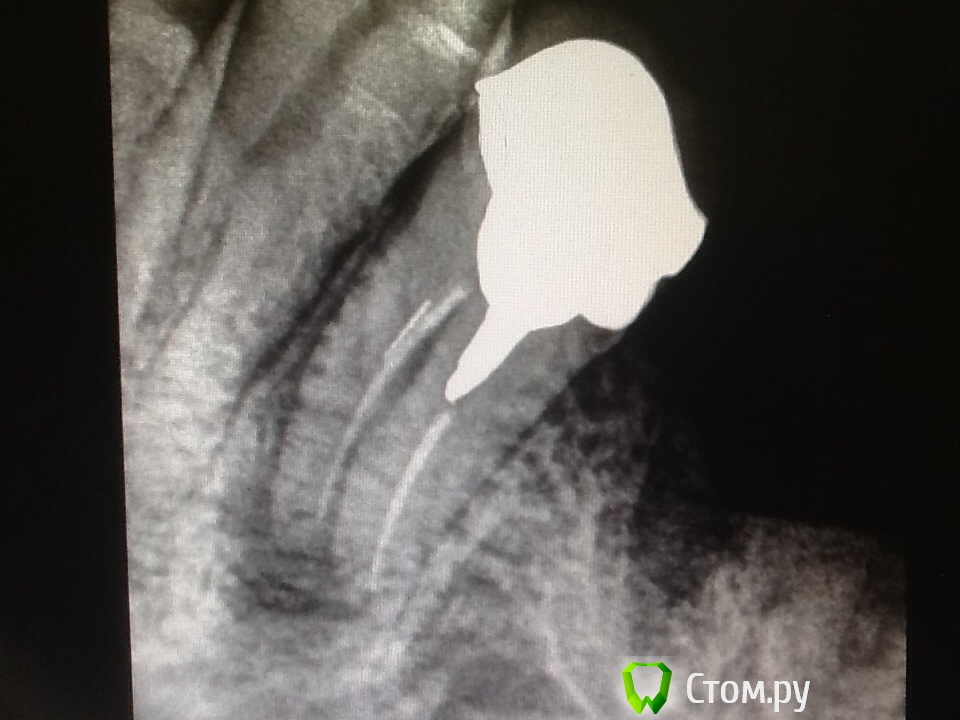

Аслан Опубликовано 12 мая, 2014 Поделиться Опубликовано 12 мая, 2014 Жалоб нет. Расцементировка коронки с временного цемента.Снимок сегодняшний.http://s16.postimg.org/4rnn19qkx/image.jpg Ссылка на комментарий

Lolopop Опубликовано 12 мая, 2014 Поделиться Опубликовано 12 мая, 2014 там инструмент в медиальном корне? попробовал бы перелечить Ссылка на комментарий

Аслан Опубликовано 12 мая, 2014 Автор Поделиться Опубликовано 12 мая, 2014 там инструмент в медиальном корне? попробовал бы перелечить да, в медиальном инструмент. Ссылка на комментарий

Аслан Опубликовано 12 мая, 2014 Автор Поделиться Опубликовано 12 мая, 2014 Окей. Идея ясна.А теперь полная история. Пацинетка обращалась в конце ноября 2012 с жалобами на боли в зубе. Тогда я еще работал протейперами. И в момент, когда я решил S2 перемерить длину мб, пассивно его опустил и он грохнулся там. Ну дальше попытки обойти, кальций, потом паковка и вкладка. Атеперь представьте, что вся эта работа совмещается с кричащим плачущим годовалым ребенком на ресепшене, и все это надо делать быстро и хорошо. http://s30.postimg.org/6qdl901wd/image.jpgНу а дальше вкладка и мк на временный. Ну и ребенок естественно все время на приеме с ней.Препаровка суровая...Сегодня пришла с грудной дочкой. Полтора года прошли не зря ))Ну и снимки в сравнении.http://s4.postimg.org/ssvjj0im1/46_2.jpg Сейчас я бы зуб в исходной ситуации удалил... Ссылка на комментарий

Аслан Опубликовано 12 мая, 2014 Автор Поделиться Опубликовано 12 мая, 2014 Аслан,Вы отломок обошли таки?Не до конца. ((( последний мм не смог... Ссылка на комментарий